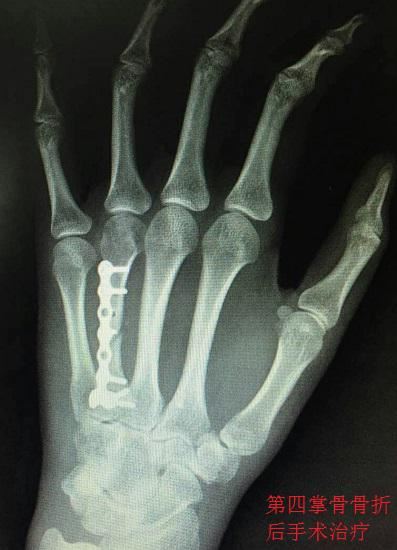

骨折后的手术治疗,通常是指切开复位内固定术,即:将骨折处的软组织切开、分离,将血管、神经等组织剖析、梳理、结扎……在肉眼可见的情况下将断骨复位,再利用坚固的材料(例如钢钉、钢丝、钢条、接骨板、克氏针等)使断骨固定,最后再将其他组织逐层复位、缝合的过程。手术治疗可以最大程度地确保骨折的复位和固定,但却会对皮肤、肌肉、血管、神经等组织造成不同程度的切割伤。无论是掌骨骨折还是指骨骨折,如果骨折后难以复位,或者复位后因为复杂的力学关系难以保持稳定,就要�򨖉�;果断实施切开复位内固定手术(也有一部分患者可以实施微创术�;�,)。需要实施手术治疗的掌骨和指骨骨折主要包括骨干和骨颈部分的斜形骨折、螺旋形骨折和粉碎性骨折,还包括开放性骨折、移位较多的关节内骨折、不稳定的骺板分离(骺板:骨骺与骨干之间的连接部)、韧带附着处撕脱型骨折、闭合性多发掌骨骨折(非重大外力导致的骨折,多存在骨折自身病变)、骨折脱位(骨折与关节脱位并存)、远节指骨掌侧基底部骨折、骨折块较大的远节指骨背侧基底部骨折等。

掌骨骨折后的手术治疗